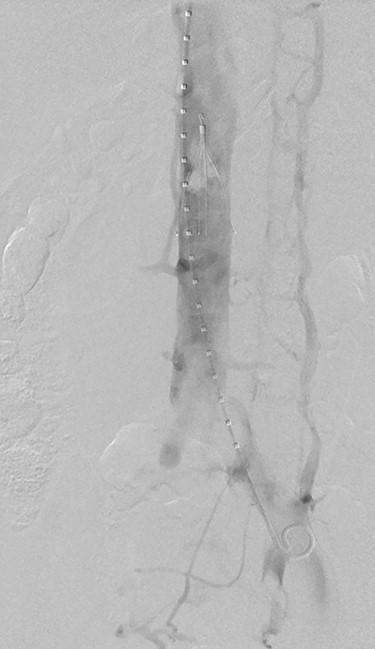

Two days after thrombectomy, a venogram of the IVC was performed to assess suitability for removal of the IVC filter. This was performed by placement of a pigtail catheter via right internal jugular vein access. This venogram illustrated fresh thrombus in IVC filter (Fig. 3), and thus, a decision was made to leave the filter in situ, remain on anticoagulation and revisit in 6 weeks to assess removal. The patient was changed to warfarin upon discharge. A venogram of the IVC was performed 6 weeks after discharge; the thrombus within the IVC filter had resolved, and the filter was successfully removed.